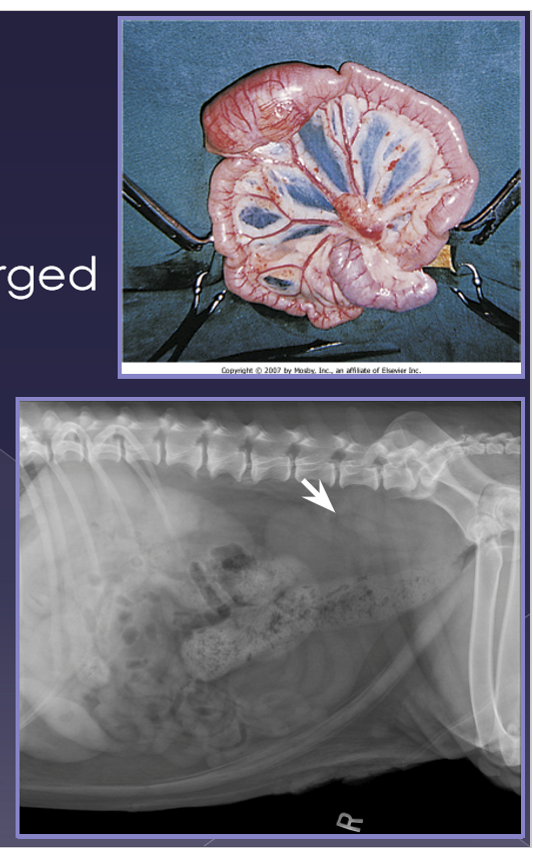

splenic torsion

spleen twists on its vascular pedicle

large breed dogs

uncommon

acute

shock, anorexia, vomiting, diarrhea, abdominal pain, enlarged spleen

chronic

anorexia, vomiting, diarrhea, abdominal pain, enlarged spleen, hemoglobinuria

radiographs

abnormal location

mass effect

gas bubbles

comma-shaped

ultrasound

variable echotexture

dilated vessels - gas bubbles

thrombi

treatment

acute more urgent than chronic

cardiovascular stabilization

antibiotics - Unasyn

electrocardiogram - can cause issues with rhyme of heart so want ECG

DO NOT UN-TWIST

Necrotic debris can enter systemic circulation

splenectomy

cannot and should not un-twist

Neoplasia of the spleen

benign or malignant

very common

large breed dogs » small breed dogs

shock, enlarged abdomen, abdominal mass, fluid wave, lethargic, vomiting, abdominal pain

same as acute but episodic presentation

diagnosis

abdominal radiographs

mass-effect

peritoneal effusion

thoracic radiographs

metastasis

mixed echotexture

cavitated lesions

enlarged spleen